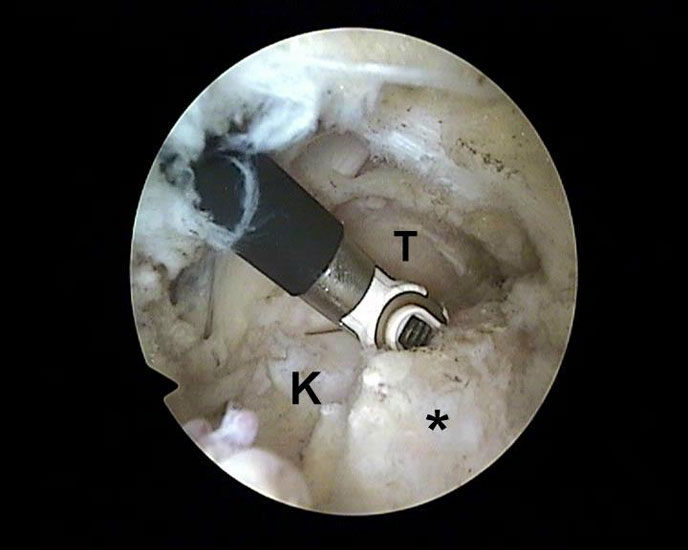

Abbildung Nr. 11-13

Das Os trigonum wird aus dem Weichteilgewebe gelöst und anschließend mit einer Fasszange entfernt. Bei größeren Knochenfragmenten muss ggf. das mediale Arthroskopieportal um wenige Millimeter verlängert werden, um die Extraktion zu ermöglichen. Nach Resektion des Os trigonum ist die posteriore Facette des Subtalargelenks erkennbar (rechte Seite, PF=posteriore Facette, FHL=Flexor hallucis longus-Sehne, T = Talus, K = Kalkaneus, *=Os trigonum).